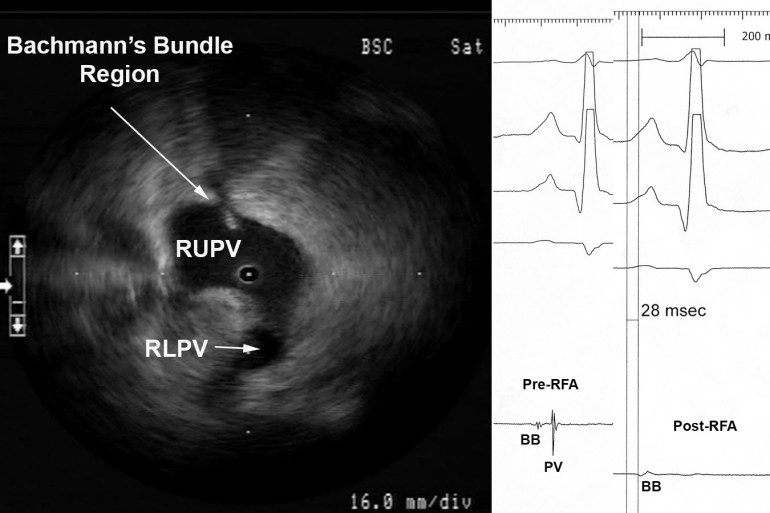

Figure 2 Myocardial Potential in the Right Upper Pulmonary Vein that may Represent Bachmann’s Bundle Potential. The ICE image shows typical right pulmonary venous antral image with the tip of ICE catheter just within the entrance to the RUPV and the RLPV obliquely viewed. The ablation catheter is located on the roof of the RUPV. A myocardial potential located ~28msec after the onset of the surface P wave is shown before (pre-RFA) and after (post-RFA) ablation of pulmonary vein (PV) potential. We surmise (though cannot prove) that this myocardial potential represents Bachmann’s bundle potential (BB).

Figure 2 shows the typical radial ICE view when positioned in the right upper pulmonary vein. There are two distinct EGM’s recorded; the earlier signal ~28 msec after the onset of the surface P wave and the later signal ~70msec after the onset of the surface P wave. The later signal represents a true pulmonary vein (PV) potential that is successfully ablated and the earlier signal remains after the ablation; we surmise (though cannot prove) this represents Bachmann’s bundle potential (BB). This signal can often be seen in the right upper pulmonary vein <30msec after the onset of the surface P wave and its presence does not reflect residual PV potentials. Bachmann’s bundle (also called the interauricular band) has a myoarchitecture that displays parallel alignment of fibers along distinct muscle bundles. [5] Bachmann’s bundle extends from the SVC, crossing the interatrial groove, passing leftward in the left atrium.